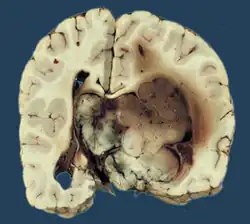

Histopathology

The tumor is neuroectodermal in origin and similar in structure to a normal choroid plexus. They may be created by epithelial cells of the choroid plexus. Papillary fronds lined by bland columnar epithelium are visible under the microscope. Normal absences include mitotic activity, nuclear pleomorphism, and necrosis.[10] Tumors have positive immunohistochemistry for cytokeratin, vimentin, podoplanin, and S-100.[11] Up to 20% of choroid plexus papilloma patients may test positive for glial fibrillary acidic protein (GFAP).[12] Studies have found that fourth ventricle cancers express more S100 than lateral ventricle tumors, and older patients (over 20 years) express more GFAP and transthyretin than younger patients.[13] Some individuals with choroid plexus papilloma have germline TP53 gene mutations, according to genetic analyses.[14] These cancers rarely exhibit nuclear p53 protein positivity. Aicardi syndrome, hypomelanosis of Ito, and 9p duplication are syndromic correlations of choroid plexus papilloma.

Micrograph of a choroid plexus papilloma. H&E stain. -

Plexuspapillom Detail -

Plexuspapillom Overview